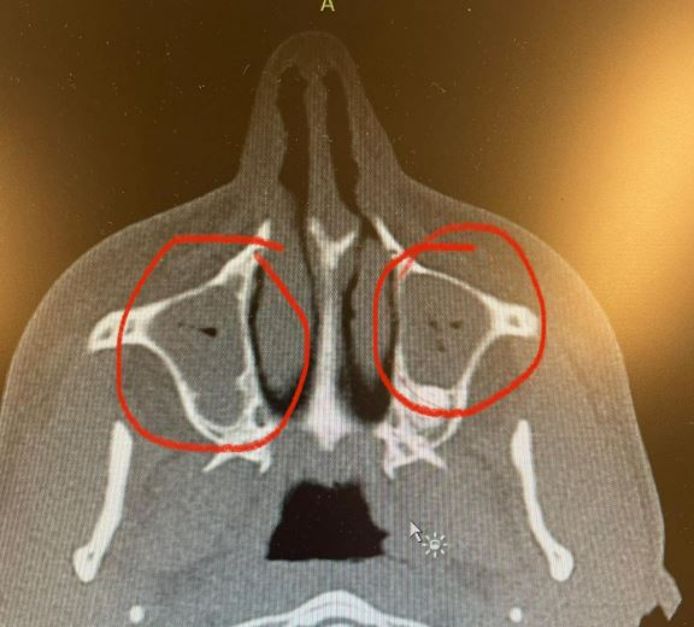

NIJMEGEN - Mart Hoogkamer zou als publiekstrekker dit weekend optreden op zowel de Zwarte Cross als de Vierdaagsefeesten, maar dat kan helaas niet doorgaan. De zanger heeft ontstoken neusholtes.

Volgens zijn management baalt Mart Hoogkamer enorm en vindt hij het heel vervelend. Op Instagram schrijft de zanger naast een echofoto van zijn neusholtes: 'Zingen is dan net zo moeilijk als op een akoestische gitaar spelen die vol zit met watten… dat lukt niet en klinkt waardeloos'. Volgens zijn management is de uitspraak dat het zou klinken als een gitaar vol watten afkomstig van de kno-arts dice ernaar gekeken heeft.

Wanneer Hoogkamer weer inzetbaar is, is niet precies bekend. De een herstelt sneller dan de ander van ontstoken neusholtes. Hij krijgt nu medicijnen om het te verhelpen.